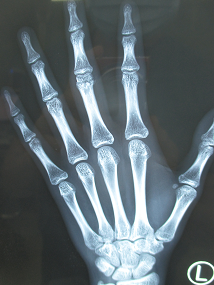

“疼、疼、疼,好疼啊!”10月15日,小鹿同学在学校里与同学玩耍时被同学扭伤左中指致肿胀,活动受限,送到我院急诊,检查发现是左中指近节指指骨骨折。

张医生赶紧安排手术行手法复位左中指近节指骨骨折,用2枚直径1.0mm钛克氏针电钻打入固定。术中透视骨折已复位,内固定在位良好。